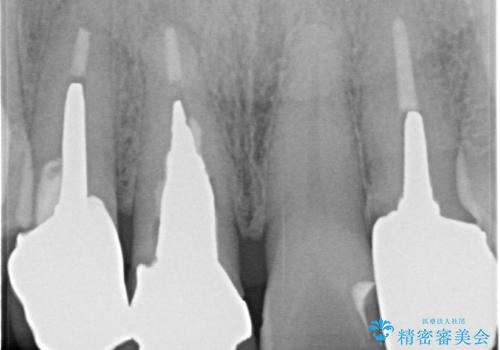

根っこの先端に病巣(根尖性歯周炎)があったため根管治療または抜歯してインプラントを提案しましたが、患者さんのご希望により被せ物の治療のみを行いました。